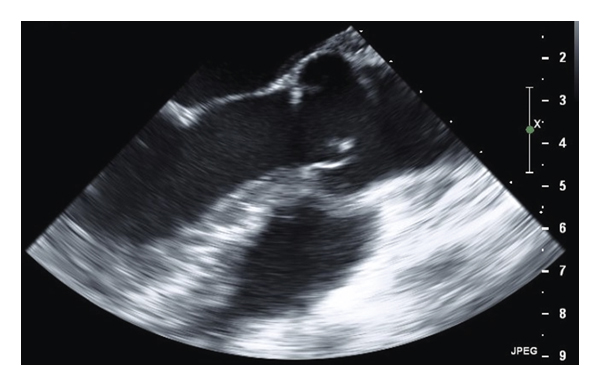

An echocardiogram was ordered when she was found to have an elevated troponin level of 0.209 ng/ml without any evidence of acute ischemic pathology on her electrocardiogram. Subsequently, a 2 cm mass was seen on the aortic valve with evidence of obstructive pathology. A follow-up transesophageal echocardiogram redemonstrated this mass, along with a smaller mass on the mitral valve associated with mild mitral regurgitation (Figure 1). The aortic mass was consistent with fresh mobile thrombus, somewhat atypical for Libman–Sacks vegetations which usually have a more verrucous appearance. However, after blood cultures and an extensive workup for culture-negative endocarditis were negative, she was ultimately diagnosed with LSE and a recurrent flare of myopericarditis.

The patient’s chest pain improved with colchicine, but her shortness of breath remained and was presumed to be from partial obstruction of the aortic valve by the large mass. After consultation with cardiothoracic surgery, medical therapy was initiated with a goal to avoid surgery if there were signs of improvement. She was already taking rivaroxaban when she originally presented, given that she had failed warfarin therapy in the past with persistently subtherapeutic INRs and recurrent DVTs, so she was started on therapeutic enoxaparin and aspirin. After a rheumatology consultation, hydroxychloroquine and prednisone were initiated as well. The patient remained stable with no new symptoms or signs of embolic events during her follow-up visits, and repeat transesophageal echocardiograms at 12 and 24 weeks demonstrated improvement in the size of both vegetations (Figure 2). Her prednisone was gradually tapered down over a period of 9 months.